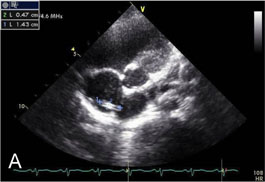

Fig. 2-A

TIVD inserted through left IJV before a removal operation.

Fig. 2-A TIVD inserted through left IJV before a removal operation.